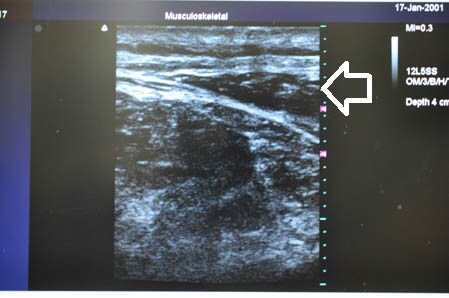

白い矢印部分が皮下脂肪層です。

上の画像の部分の皮下脂肪層を

つまんでみることにしましょう。